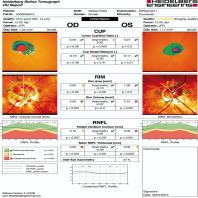

- eFig. 9-3 - Relevé d'écran d'accueil HRT

- eFig. 9-4 - Ligne de contour et plan de référence HRT

- eFig. 9-5 - Données stéréométriques

- eFig. 9-6 - Analyse de régression de Moorfields

- eFig. 9-7 - Score de probabilité de glaucome

- eFig. 9-8 - Tracé interactif HRT